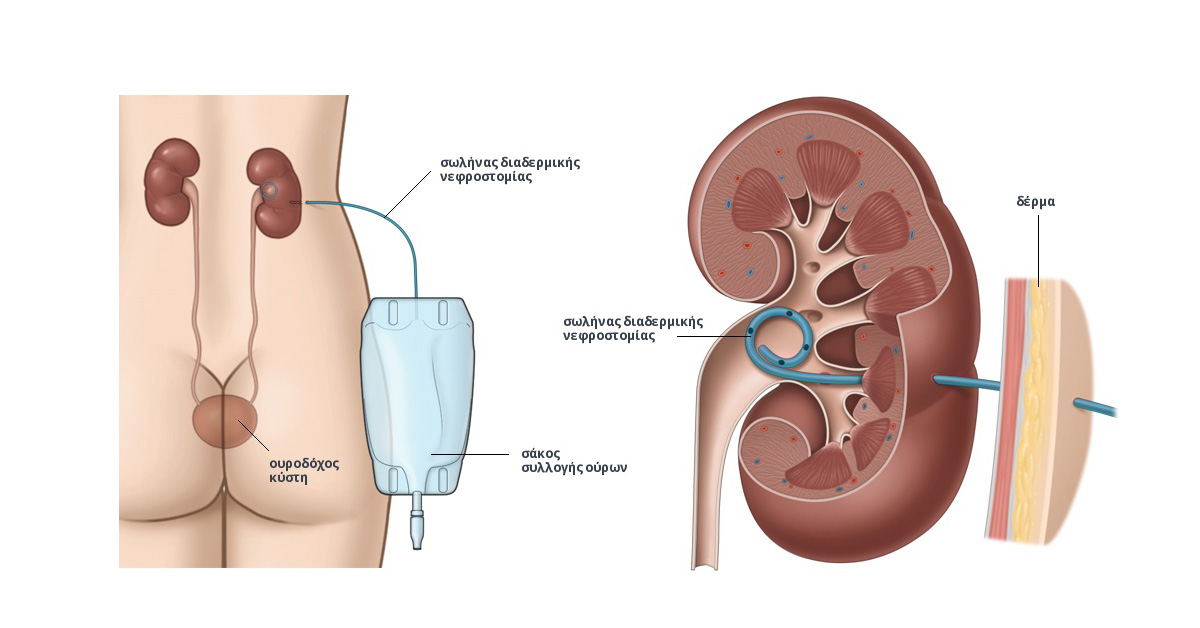

Трансплантация почек стала одной из основных методик лечения для людей, нуждающихся в почечной поддержке.

Современные технологии дозволяют проводить диализ, протягивая время для тех, кто не может жить без помощи аппаратов.

Как жить без почки?